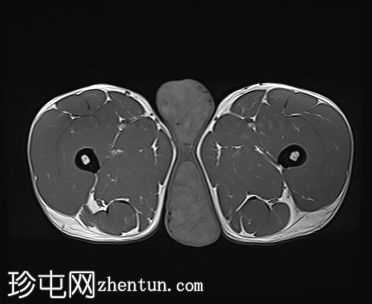

轴位

T2加权像

3.jpg

阴囊内睾丸增大,T1加权像上可见分叶状软组织病变,呈中高信号,T2加权像上呈低信号。

轻度双侧鞘膜积液。

本病例表现为双侧睾丸肿胀,影像学特征符合睾丸肾上腺残余肿瘤的典型表现,即T1加权像上呈双侧中高信号,T2加权像上呈低信号。